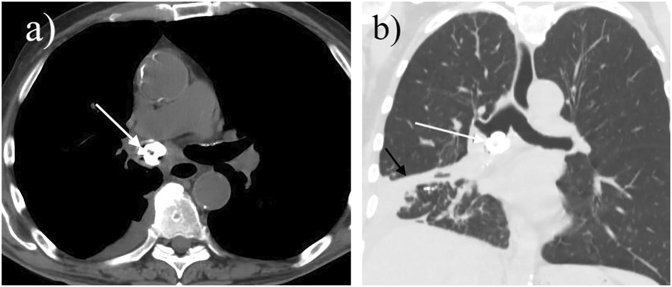

获得性良性气管食管瘘和支气管食管瘘(TEF)通常与肉芽肿性纵隔感染有关,其中75%是先天性的。白色念珠菌(Candida albicans)和放线菌(Actinomyces)是常见的病原体,但 TEF 的病因并不常见。这些病原体的正常定植和某些种类生长缓慢的特点很少导致感染、霉菌瘤和支气管胆石症,因此很可能延误诊断和治疗。很少有报道称白僵菌或放线菌是 TEF 或支气管胆石症的病原体。在此,我们报告了一例继发于白色念珠菌和放线菌共同感染的良性获得性 TEF 病例,该病例并发放线菌瘤的形成和支气管胆石症,我们还进行了全面的文献综述,以强调该病例的特殊性,并提供 TEF 的诊断和治疗算法。在出现三个月的有痰咳嗽、窒息感、盗汗和体重减轻后,支气管镜检查发现食管和右中叶后部之间有瘘管连接。病理检查发现了一个钙化的真菌球和一个继发于念珠菌和放线菌共同感染的支气管结石。这种念珠菌和放线菌合并感染的独特表现形式以及相关的诊断算法将为临床医生提供教育和有用的工具。

Acquired benign tracheoesophageal fistulas and bronchoesophageal fistulas (TEF) are typically associated with granulomatous mediastinal infections, 75% of which are iatrogenic. Candida albicans and Actinomyces are commonly occurring organisms, but are uncommon etiologies of TEF. Normal colonization and the slow growth characteristics of some species of these agents rarely result in infection, mycetoma, and broncholithiasis, and thus, delays in diagnosis and treatment are likely. Few reports describe C. albicans or Actinomyces spp. as the etiology of TEF or broncholithiasis. Herein, we report a case of benign acquired TEF secondary to coinfection of Candida and Actinomyces complicated by the formation of an actinomycetoma and broncholithiasis and a comprehensive literature review to highlight the unique nature of this presentation and offer a diagnostic algorithm for diagnosis and treatment of TEFs. Following a presentation of three months of productive cough, choking sensation, night sweats, and weight loss, a bronchoscopy revealed a fistulous connection between the esophagus and the posterior right middle lobe. Pathology identified a calcified fungus ball and a broncholith secondary to the co-infection of Candida and Actinomyces. This unique presentation of Candida and Actinomyces co-infection and the associated diagnostic algorithm are presented as education and a useful tool for clinicians.